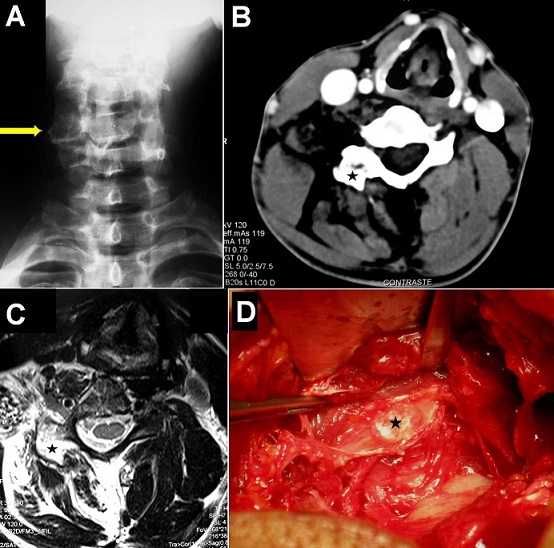

A 48-year-old man was referred to our unit for assessment of recurring episodes of painful torticollis. Family and past histories were unremarkable. There was no traumatic antecedent. During the previous three years he had experienced several episodes of torticollis and painful cervical movements without radiculopathy. His neurological examination was normal, except for a head tilt, decrease range of cervical motion and local tenderness on the right lateral side of the neck. Cervical spine radiographs showed a cervical scoliosis with right unilateral C5-C6 facet joint hypertrophy (A). Cervical computed tomography-scan and magnetic resonance imaging demonstrated a small bone regular tumor in the right C6 articular process and important amyotrophia of the neck musculature on the right side without nerve root or spinal cord compression (B and C). A posterior cervical approach was performed and the mass was completely removed without facet joint sacrifice. At surgery, the tumor appeared well-circumscribed, firm, and calcified with a cartilaginous-cap like appearance (D). Histological features were consistent with benign osteochodroma. The patient was discharged home pain free and referred for physiotherapy care with a good outcome. Osteochondroma is the most common benign tumor of bone (especially long bones), but the spine is rarely involved and usually indicates a hereditary cause such as osteochondromatosis (hereditary multiple exostosis). As seen in our case, this lesion is slow growing, and therefore significant spinal deformation can occur before the symptoms are recognized.